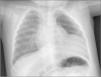

En la radiografía de tórax (fig. 1) se aprecia una ocupación supradiafragmática izquierda con borde superior neto convexo que hace signo de la silueta con el ápex cardíaco y respeta la parte lateral del hemidiafragma.

Se revisa la historia clínica observándose en la radiografía de tórax del período neonatal una imagen de ocupación supradiafragmática izquierda que no fue tenida en consideración dada la importante rotación del paciente y la nula sintomatología.